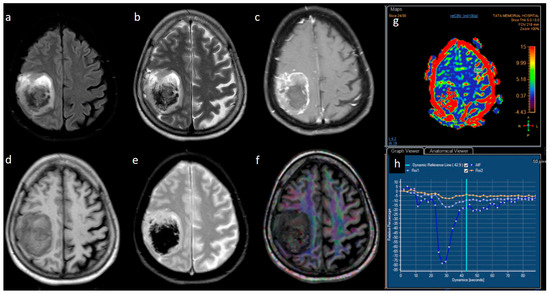

3.2. MRI Parameters of IDH-Wildtype vs. Mutant Phenotype Tumors

| Variable | Parameter | IDH-Mutated (n = 19) | IDH-Wildtype (n = 129) | p-Value |

|---|---|---|---|---|

| Enhancement I | Mild | 9 (47.4) | 5 (3.9) | <0.001 |

| Moderate | 6 (31.6) | 25 (19.4) | ||

| Severe | 4 (21.1) | 99 (76.7) | ||

| Enhancement III | Rim | 6 (31.6) | 104 (80.6) | <0.001 |

| Nodular | 0 | 2 (1.6) | ||

| Patchy | 11 (57.9) | 13 (10.1) | ||

| Solid | 2 (10.5) | 10 (7.8) | ||

| Necrosis | None | 3 (15.8) | 3 (2.3) | <0.001 |

| <25% | 11 (57.9) | 14 (10.9) | ||

| 25- 50% | 2 (10.5) | 35 (27.1) | ||

| >50% | 3 (15.8) | 77 (59.7) | ||

| Dural enhancement | AbsentPresent | 07 (70.0) | 31 (24.0)48 (52.7) | 0.013 |

| Edema | None | 3 (15.8) | 3 (2.3) | 0.025 |

| <tumor volume | 11 (57.9) | 68 (52.7) | ||

| Equal to tumor volume | 4 (21.1) | 35 (27.1) | ||

| >tumor volume | 1 (5.3) | 23 (17.8) | ||

| Cysts * | No | 11 (57.9) | 115 (89.1) | 0.001 |

| Yes | 6 (31.6) | 14 (10.9) | ||

| Subcortical involvement | Involved | 18 (94.7) | 94 (72.9) | 0.044 |

| Not involved | 1 (5.3) | 35 (27.1) | ||

| rCBV | Median (IQR) | 1.8 [1.4–2.0] | 2.6 [1.9–3.5] | 0.001 |